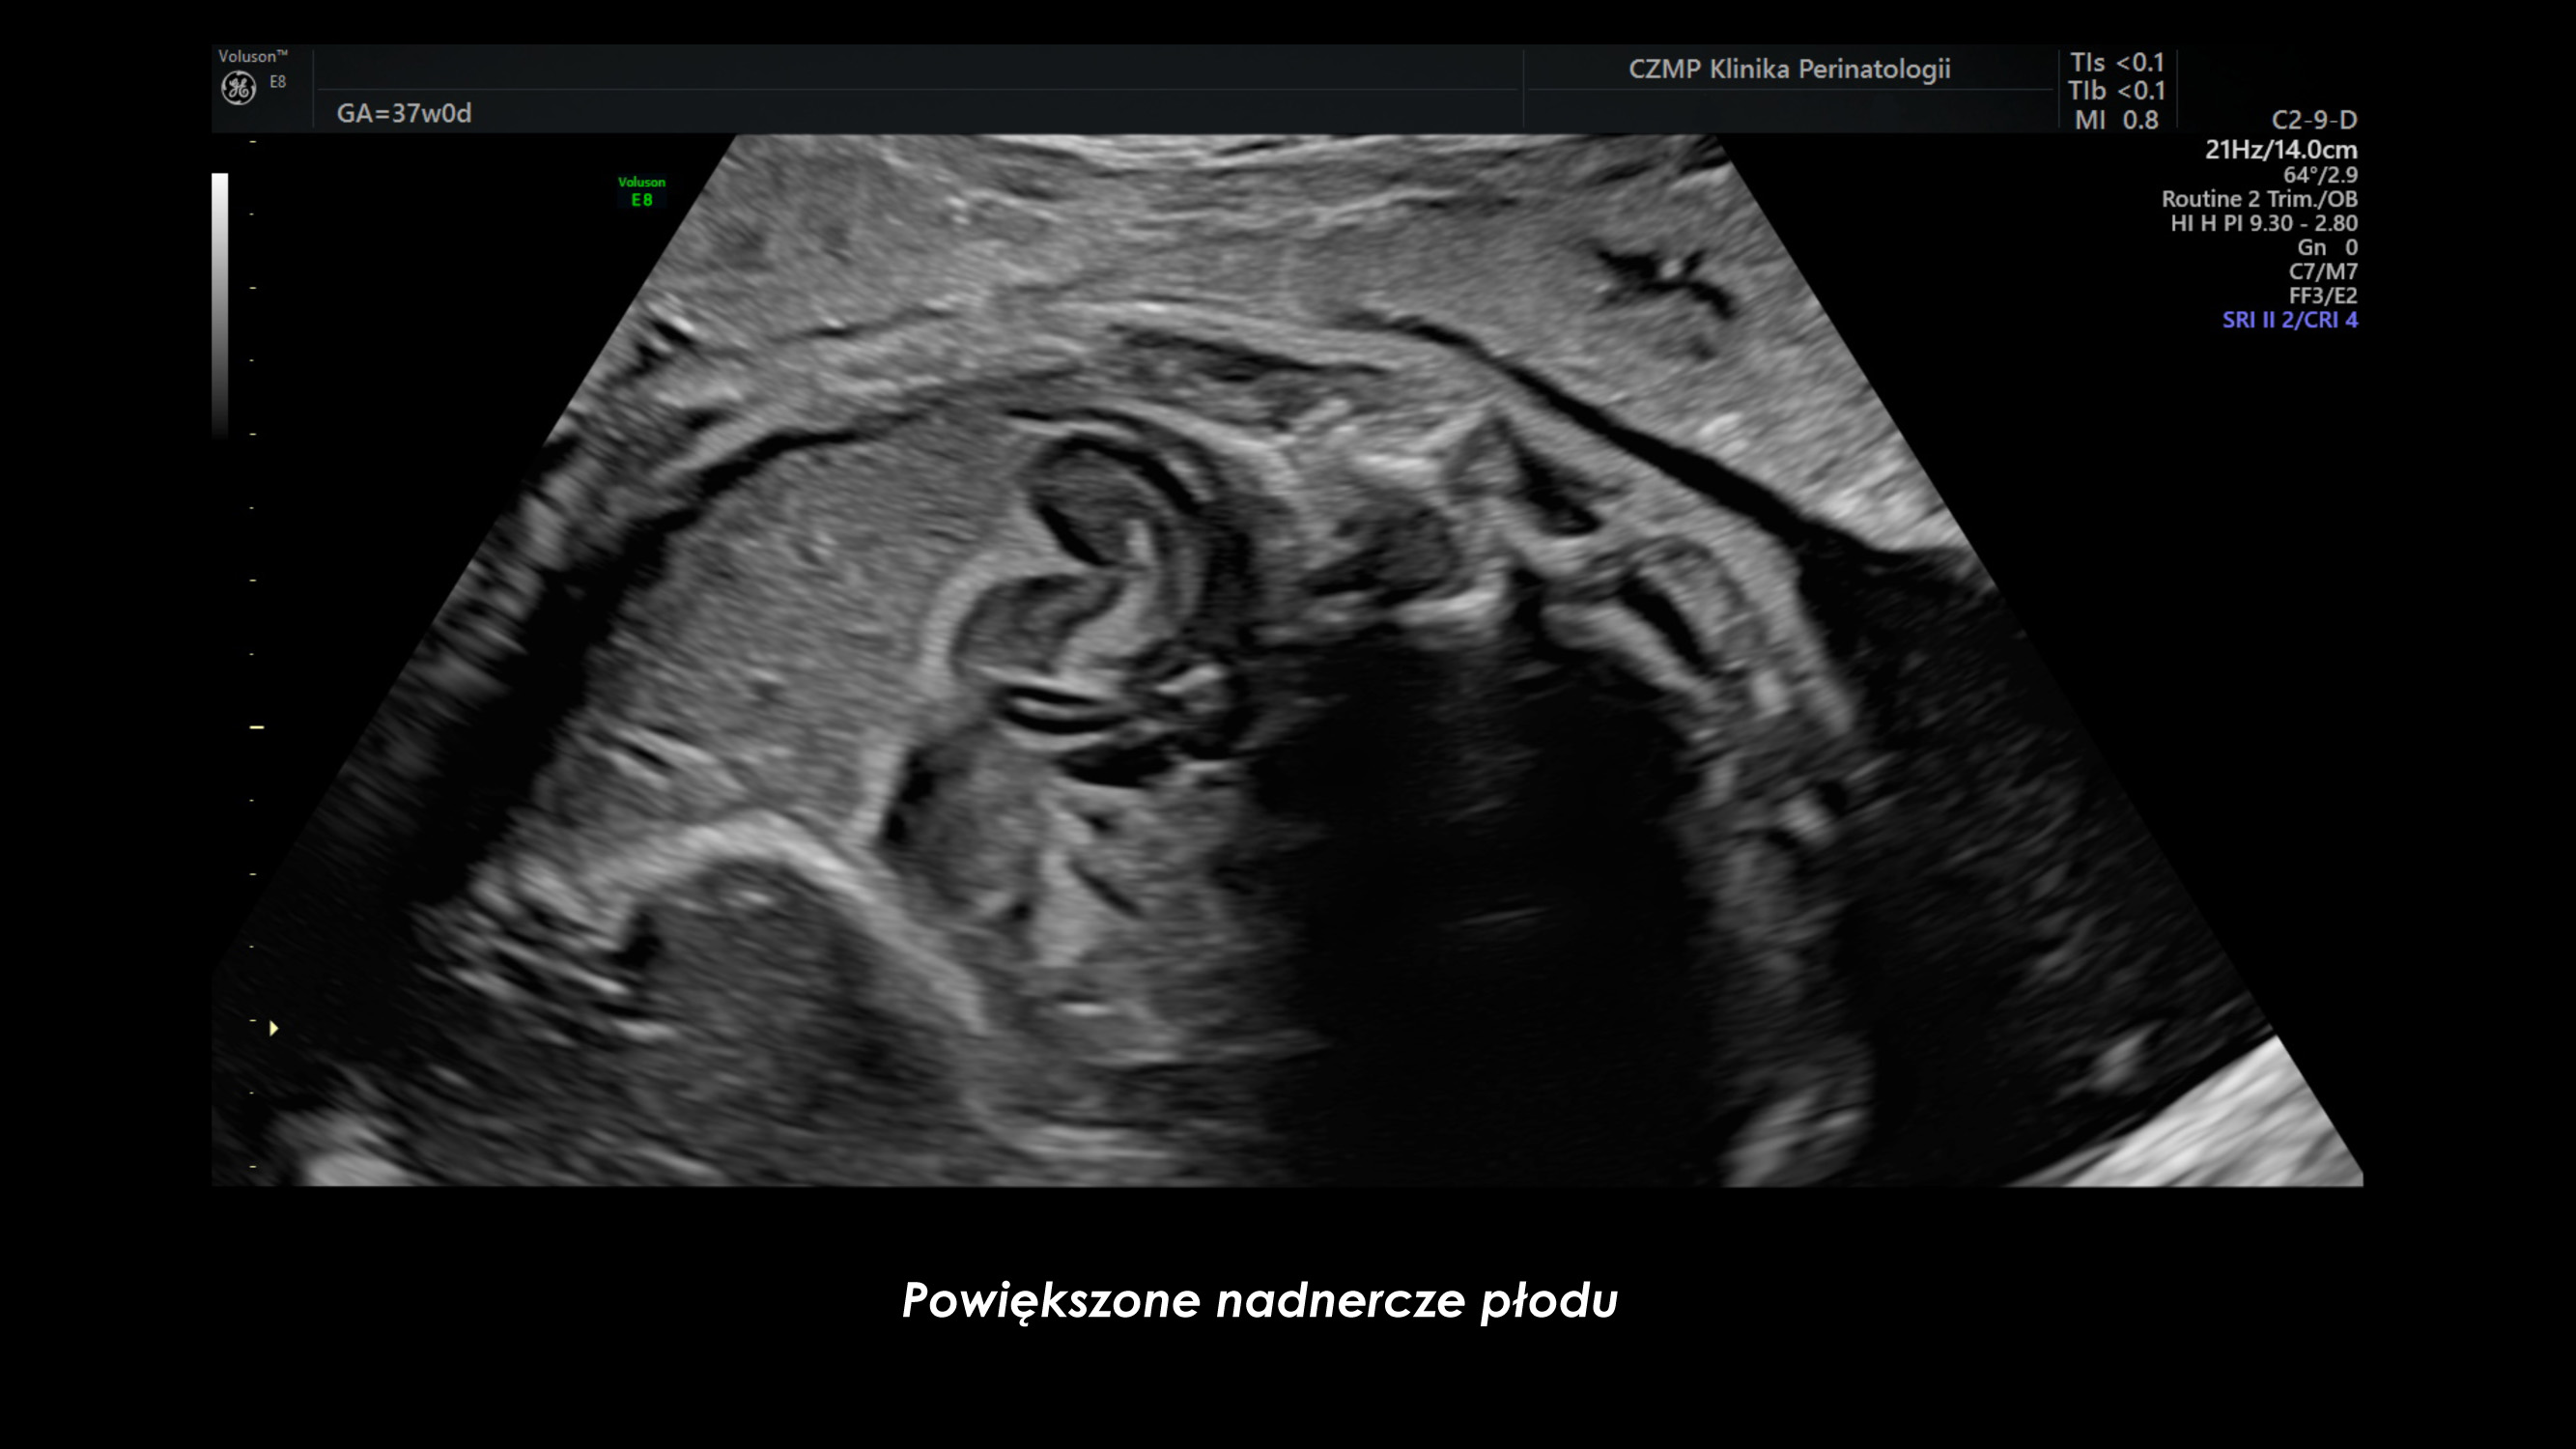

Nietypowy guz jamy brzusznej płodu